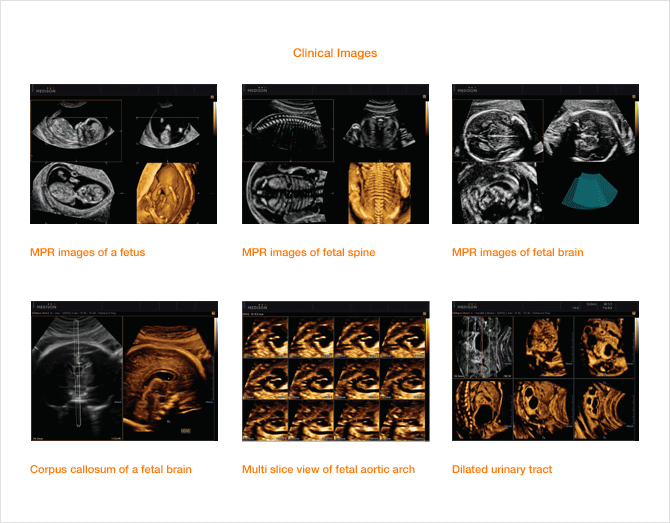

A következő generációs technológia a jelenben, amely drámaian javítja a 3D képek minőségét.

HDVI™ is based on non stationary adaptive filtering resulting in removal of unwanted speckle and noise whilst increasing visualization of edges and small structures in volume data. HDVI™ uses a 3D processing algorithm that is based on 3D matrix processing of volume data.

The essential feature of this 3D processing algorithm is matrix image processing which allows more accurate rendered information calculated from the voxel data of the acquired volume data.

By using this calculation method, a clear and improved image is shown in the rendered and multi-planar views.

HD Volume Imaging™ Performance

HD Volume Imaging™ (HDVI™) removes artifacts and incorporates a speckle reduction filter without compromising details but at the same time emphasizing the edge and structures. Therefore, 3D rendered image and multi-planar view provides an image quality with improved contrast and resolution. According to the result, it shows that the speckle noise of the image with HDVI™ is lower while the edge enhancement are higher, compared to the Original.

Additional effect of HDVI™ and OVIX™

HDVI™ image has amplified effect if used in conjunction with OVIX™(Oblique View eXtended). OVIX™ reduces noise and increases contrast by compounding multiple images. The pictures show the synergy of HDVI™ and OVIX™ when they are used together.